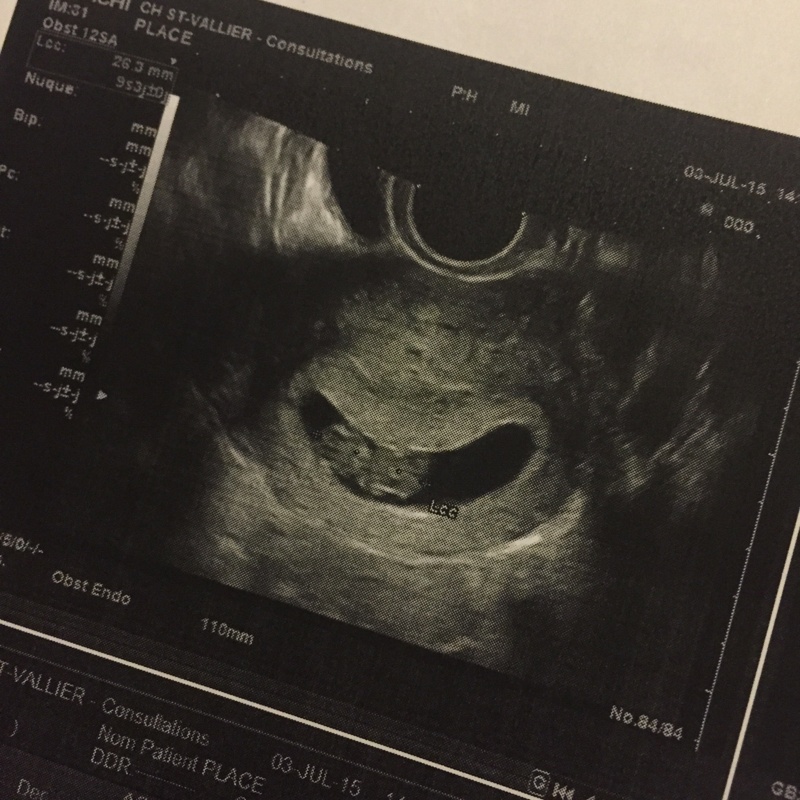

2,6cm pour mon ptit asticot qui bougeait ses petites jambes

• image-2487117004.jpg

image-2487117004.jpg

214.4 KB · Affichages: 155

2,6cm pour mon ptit asticot qui bougeait ses petites jambes Prochain rdv le 24/07 Elle ma dit que elle me prolongerait l'arret si je le souhaitais :) On verra ca Je continue la progestérone et le spasfon jusquau 12sa Me voila rassurée